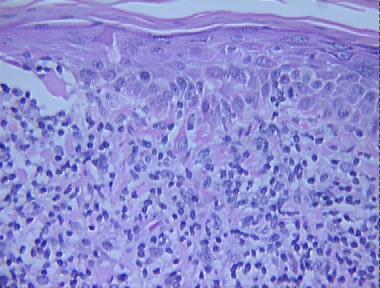

actinic keratosis, lichenoid type

actinic keratosis, lichenoid typeBuy A Systematic Approach to Dermatopathology on Amazon.com

Histologic Features